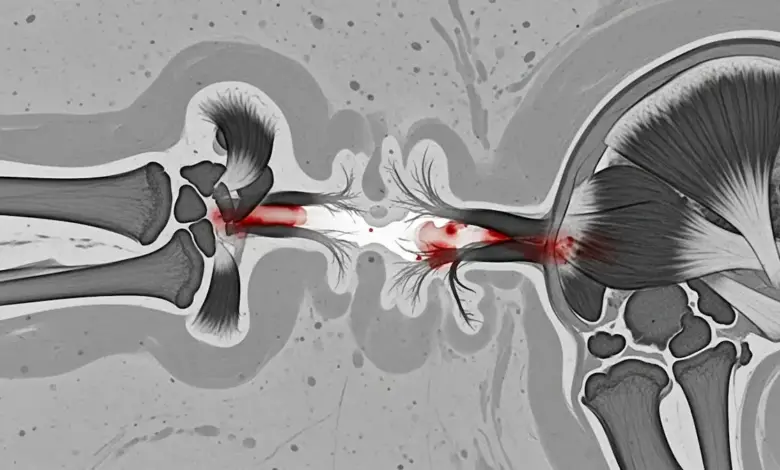

A ruptura do tendão distal do tríceps é rara, mas pode comprometer bastante a função do cotovelo. Esse tendão fixa o músculo tríceps no olécrano, a proeminência óssea na ponta do cotovelo.

A ruptura distal costuma ocorrer perto do ponto onde o tendão se fixa no olécrano. É nessa região que a carga aumenta em movimentos de empurrar, apoiar o corpo e “travar” o braço.

Em rupturas completas, pode existir uma depressão palpável acima do olécrano e uma alteração no contorno do tríceps.

O objetivo é reinserir o tendão no olécrano, restaurando o braço de alavanca do tríceps e permitindo recuperação de força.